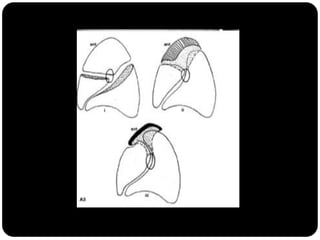

Atelectasia

 Diminuição de volume do segmento, deslocamento de uma ou mais

fissuras interlobares em direção à parte atelectasiada, desvio do mediastino

para o lado envolvido, deslocamento hilar, estreitamento dos espaços

intercostais e hiperinsuflação dos outros lobos / segmentos não atelectasiados

de forma compensatória.

Ex: Colapso do

LSD

Observar

deslocamento de

fissura!

Atelectasia do lobo

superior direito

Atelectasia do Lobo Sup. D.